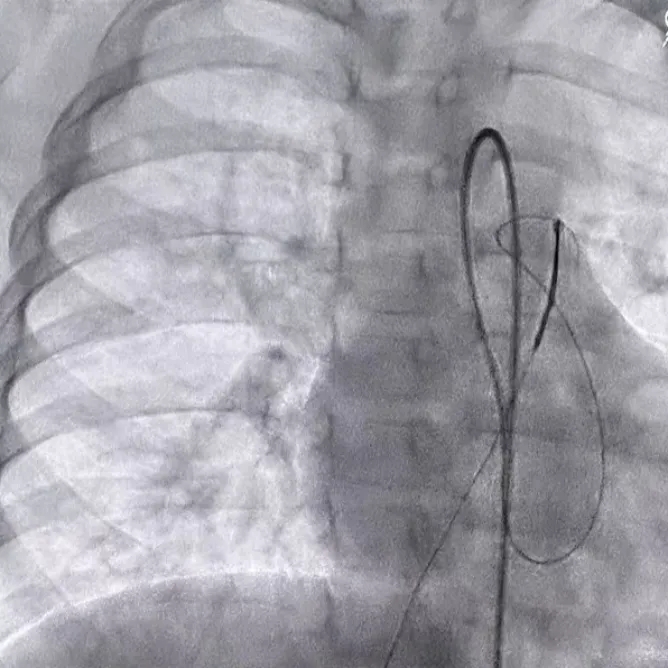

轨道建立

在肺动脉内圈套导丝,建立动静脉轨道

沿导丝送入输送鞘,并将输送鞘压入左心室